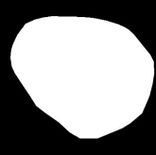

Figure 6 illustrates the segmentation outcomes attained with different neural networks using the same dataset. The enhanced U-Net network proposed in this study is evaluated alongside expert gold standards, Swin-Unet, U-Net, and other well-known network models. The segmentation results from the Swin-Unet network show jagged edges and less smooth nodule edge segmentation, leading to suboptimal outcomes. In the case of U-Net, there are evident under-segmentations with significant discrepancies in the segmented area of some nodules, resulting in inaccurate segmentation results. However, the use of the improved U-Net network introduced in this research produces smoother edges of the segmented thyroid nodules, and the edge contours more closely align with those of the expert gold standard. Moreover, the errors in shape and segmented area are smaller compared to those seen with U-Net and Swin-Unet. The findings suggest that the improved U-Net network provides superior performance in thyroid nodule segmentation.